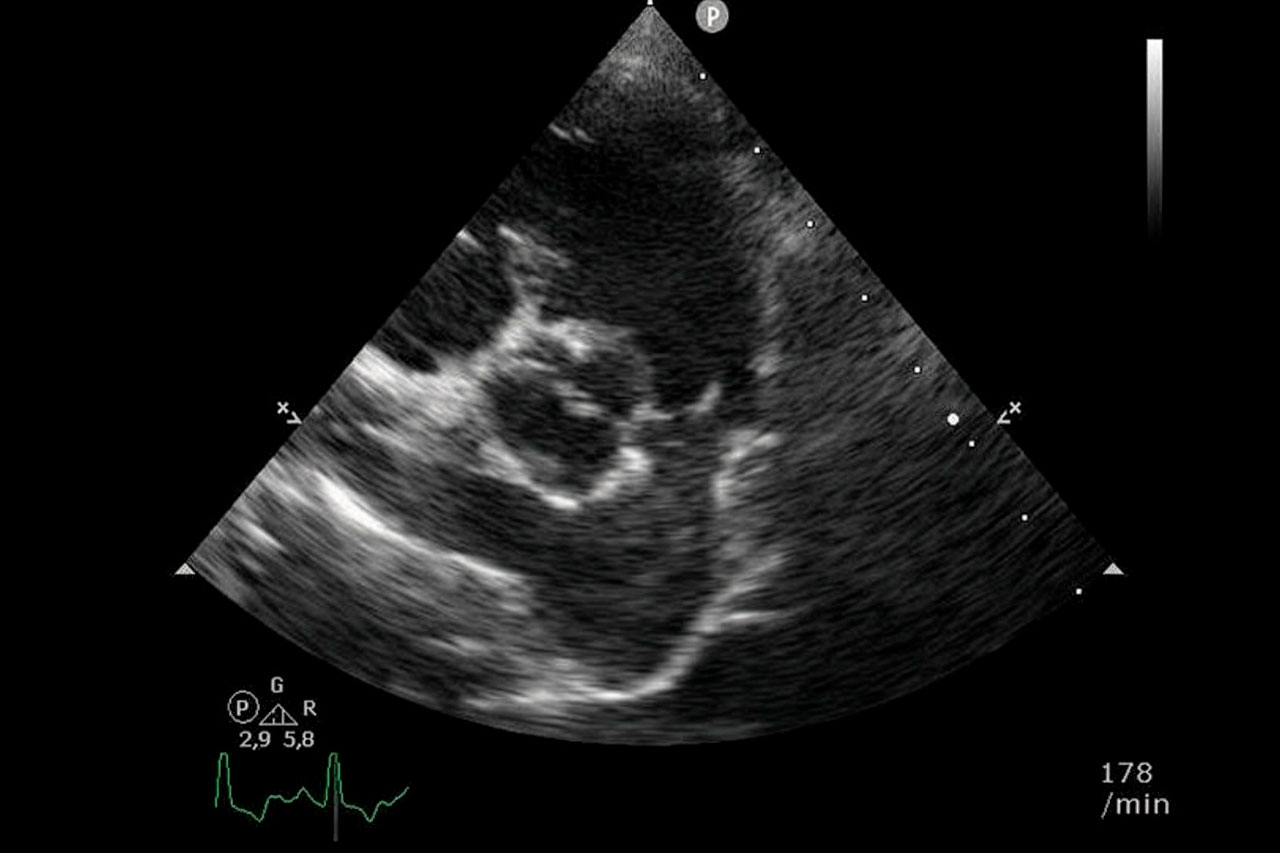

Echokardiographie: Mit Ultraschall wird das Herz genauer untersucht, um die Diagnose zu stellen und den Schweregrad der Verengung einzuschätzen.

Impressionen zur Ballonvalvuloplastie